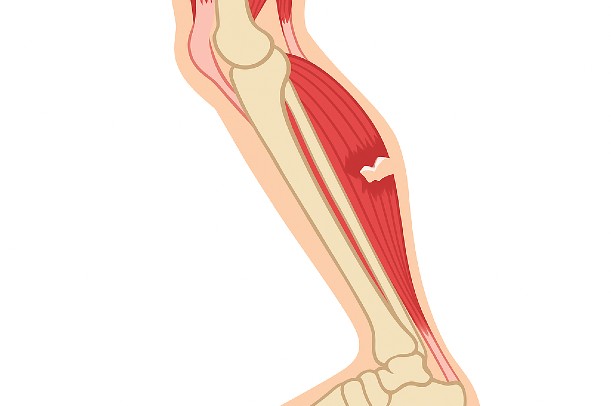

肉離れが特に起こりやすいのは太ももの裏側にある「ハムストリング」です。全力疾走やジャンプの動作で強く使われる筋肉であり、損傷リスクが高いとされています。次に多いのは太ももの前にある「大腿四頭筋」、さらに「内転筋」や「ふくらはぎ(腓腹筋)」も好発部位として知られています(引用元:https://sincellclinic.com/column/what-is-muscle-strain )。

これらの筋肉はスポーツの場面で酷使されやすいですが、日常生活の中でも負担がかかることがあります。そのため、学生アスリートだけでなく、運動不足の状態で急に体を動かした中高年層でも発生する可能性があると考えられています。